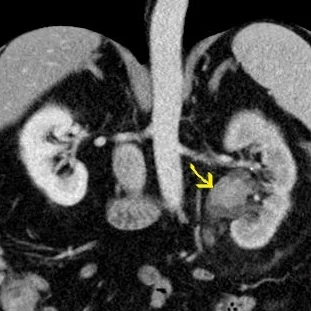

71 yo M presented with acute onset left abdominal pain. He was previously scheduled for a urology appointment to work-up a urothelial mass, but came to the ED for acute onset pain.

Conventioanl CT shows a filling defect in the left renal collecting system. Iodine uptake seen on the fusion image confirms vascular lesion. Note the delayed nephrogram on the left consistent with obstruction from the mass.

Conventional image with filling defect in left renal pelvis (yellow arrow)